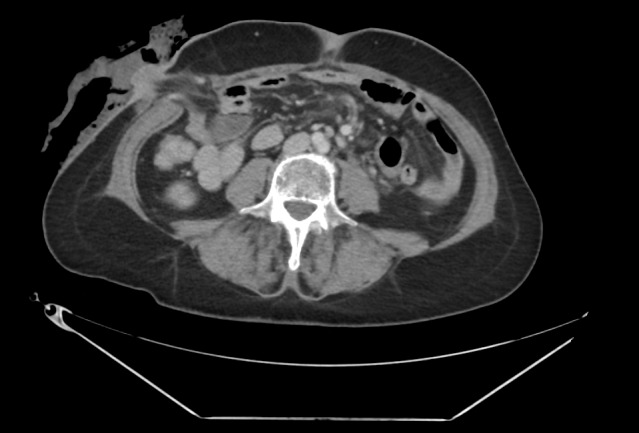

Temporary loop ileostomies are common after colorectal cancer surgery to reduce anastomotic leak severity. However, ileostomy takedown carries risks like surgical site infections (SSIs) and incisional hernias. The optimal fascial closure technique during takedown remains debated. This study compared these techniques regarding postoperative complications. This retrospective study analyzed data from 69 patients undergoing scheduled loop ileostomy closure between 2016-2020 at two Romanian surgical departments. Data collected included demographics, clinical variables (ASA score, comorbidities), surgical details (suture type, closure time, skin closure type), and follow-up data including CT assessments for hernia detection. The cohort included 69 patients (mean age 63, 64% male). Fascial closure was used in 17 (24.7%) and interrupted in 52 (75.4%) patients. Running sutures were significantly faster (mean 19 vs. 22 min, p=0.028). Overall SSI rate was 21.7%. Ileostomy site incisional hernias occurred in 13 patients (18.6%) after a mean follow-up of 30.7 months. No statistically significant difference in hernia rates was found between running (3/17) and interrupted (10/52) suture groups (p=1). Significant risk factors for hernia development included longer follow-up (OR=0.87, p=.025), BMI≥30 (OR=176, p=.009), and Clavien-Dindo grade 3 postoperative complications (OR=112, p=.033). While running sutures offer faster fascial closure, this study found no significant difference in ileostomy site incisional hernia rates between running and interrupted techniques. Patient factors like BMI ≥30 and severe postoperative complications are significant predictors of hernia formation. Careful technique is crucial, but primary closure without mesh remains standard.

Abstract Image